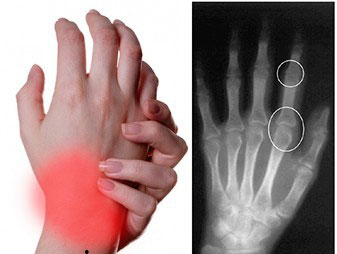

- рентгенография пораженных суставов не выявляет специфических изменений при реактивном процессе, но используется для дифференциальной диагностики с другими видами артритов, также могут применяться УЗИ крупных суставов, КТ, МРТ и другие исследования;